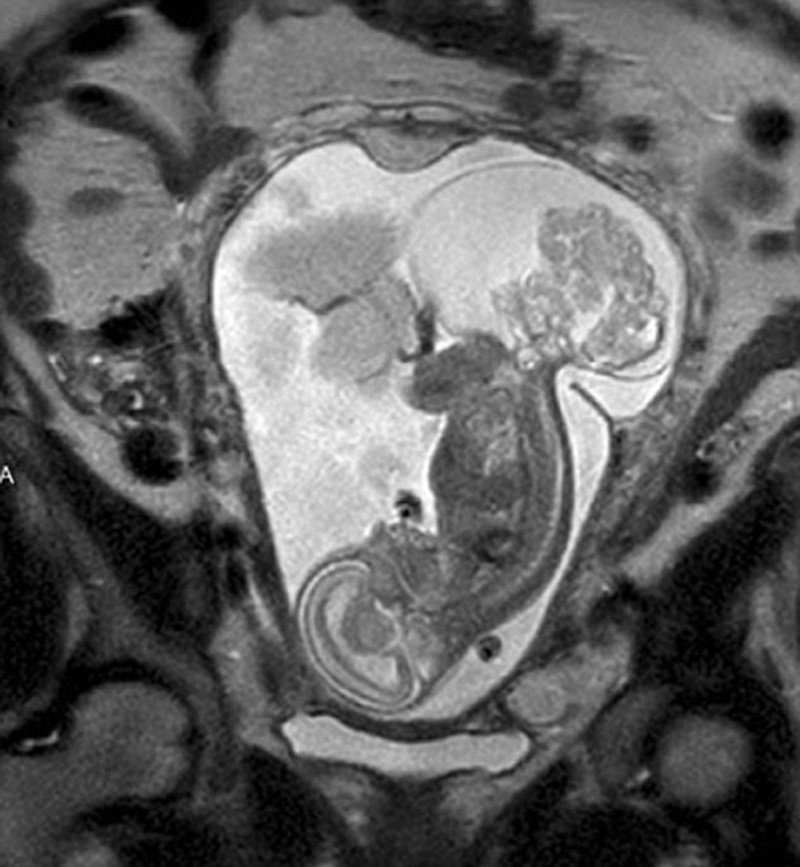

Η μητέρα της μικρής, η Μάργκαρετ, διήνυε την 16η εβδομάδα της κύησης της, όταν μετά από επίσκεψη στον γιατρό ενημερώθηκε ότι το έμβρυο είχε ένα ιεροκοκκυγικό τεράτωμα: είχε αναπτυχθεί ένας όγκος στην περιοχή του ιερού οστού και του κόκκυγά του – κάτι που παρουσιάζεται σε 1 στις 30.000-70.000 γεννήσεις.

Ο όγκος αναπτυσσόταν ραγδαία και τρεφόταν από το αίμα του εμβρύου, κάτι που σταδιακά θα προκαλούσε καρδιακή ανεπάρκεια και θα οδηγούσε στον θάνατό του. Ο μόνος τρόπος για να σωθεί, ήταν να υποβληθεί σε μια πρωτοποριακή και συνάμα επικίνδυνη χειρουργική επέμβαση, που πρότειναν οι γιατροί της εμβρυϊκής κλινικής του Νοσοκομείου Παίδων του Τέξας και η οποία απαιτούσε την εξαγωγή του εμβρύου από τη μήτρα της μητέρας του.

Μετά από 28 εβδομάδες κύησης οι γιατροί έβγαλαν το έμβρυο από τη μήτρα της μητέρας του και κατάφεραν να αφαιρέσουν τον όγκο σε μια πολύπλοκη επέμβαση, που διήρκεσε πέντε ολόκληρες ώρες.

Στη συνέχεια οι γιατροί τοποθέτησαν και πάλι το έμβρυο στη μήτρα της μητέρας του, και 12 εβδομάδες αργότερα η Λίνλι ήρθε στον κόσμο με καισαρική για να (ξανα)αντικρίσει το φως της ζωής...